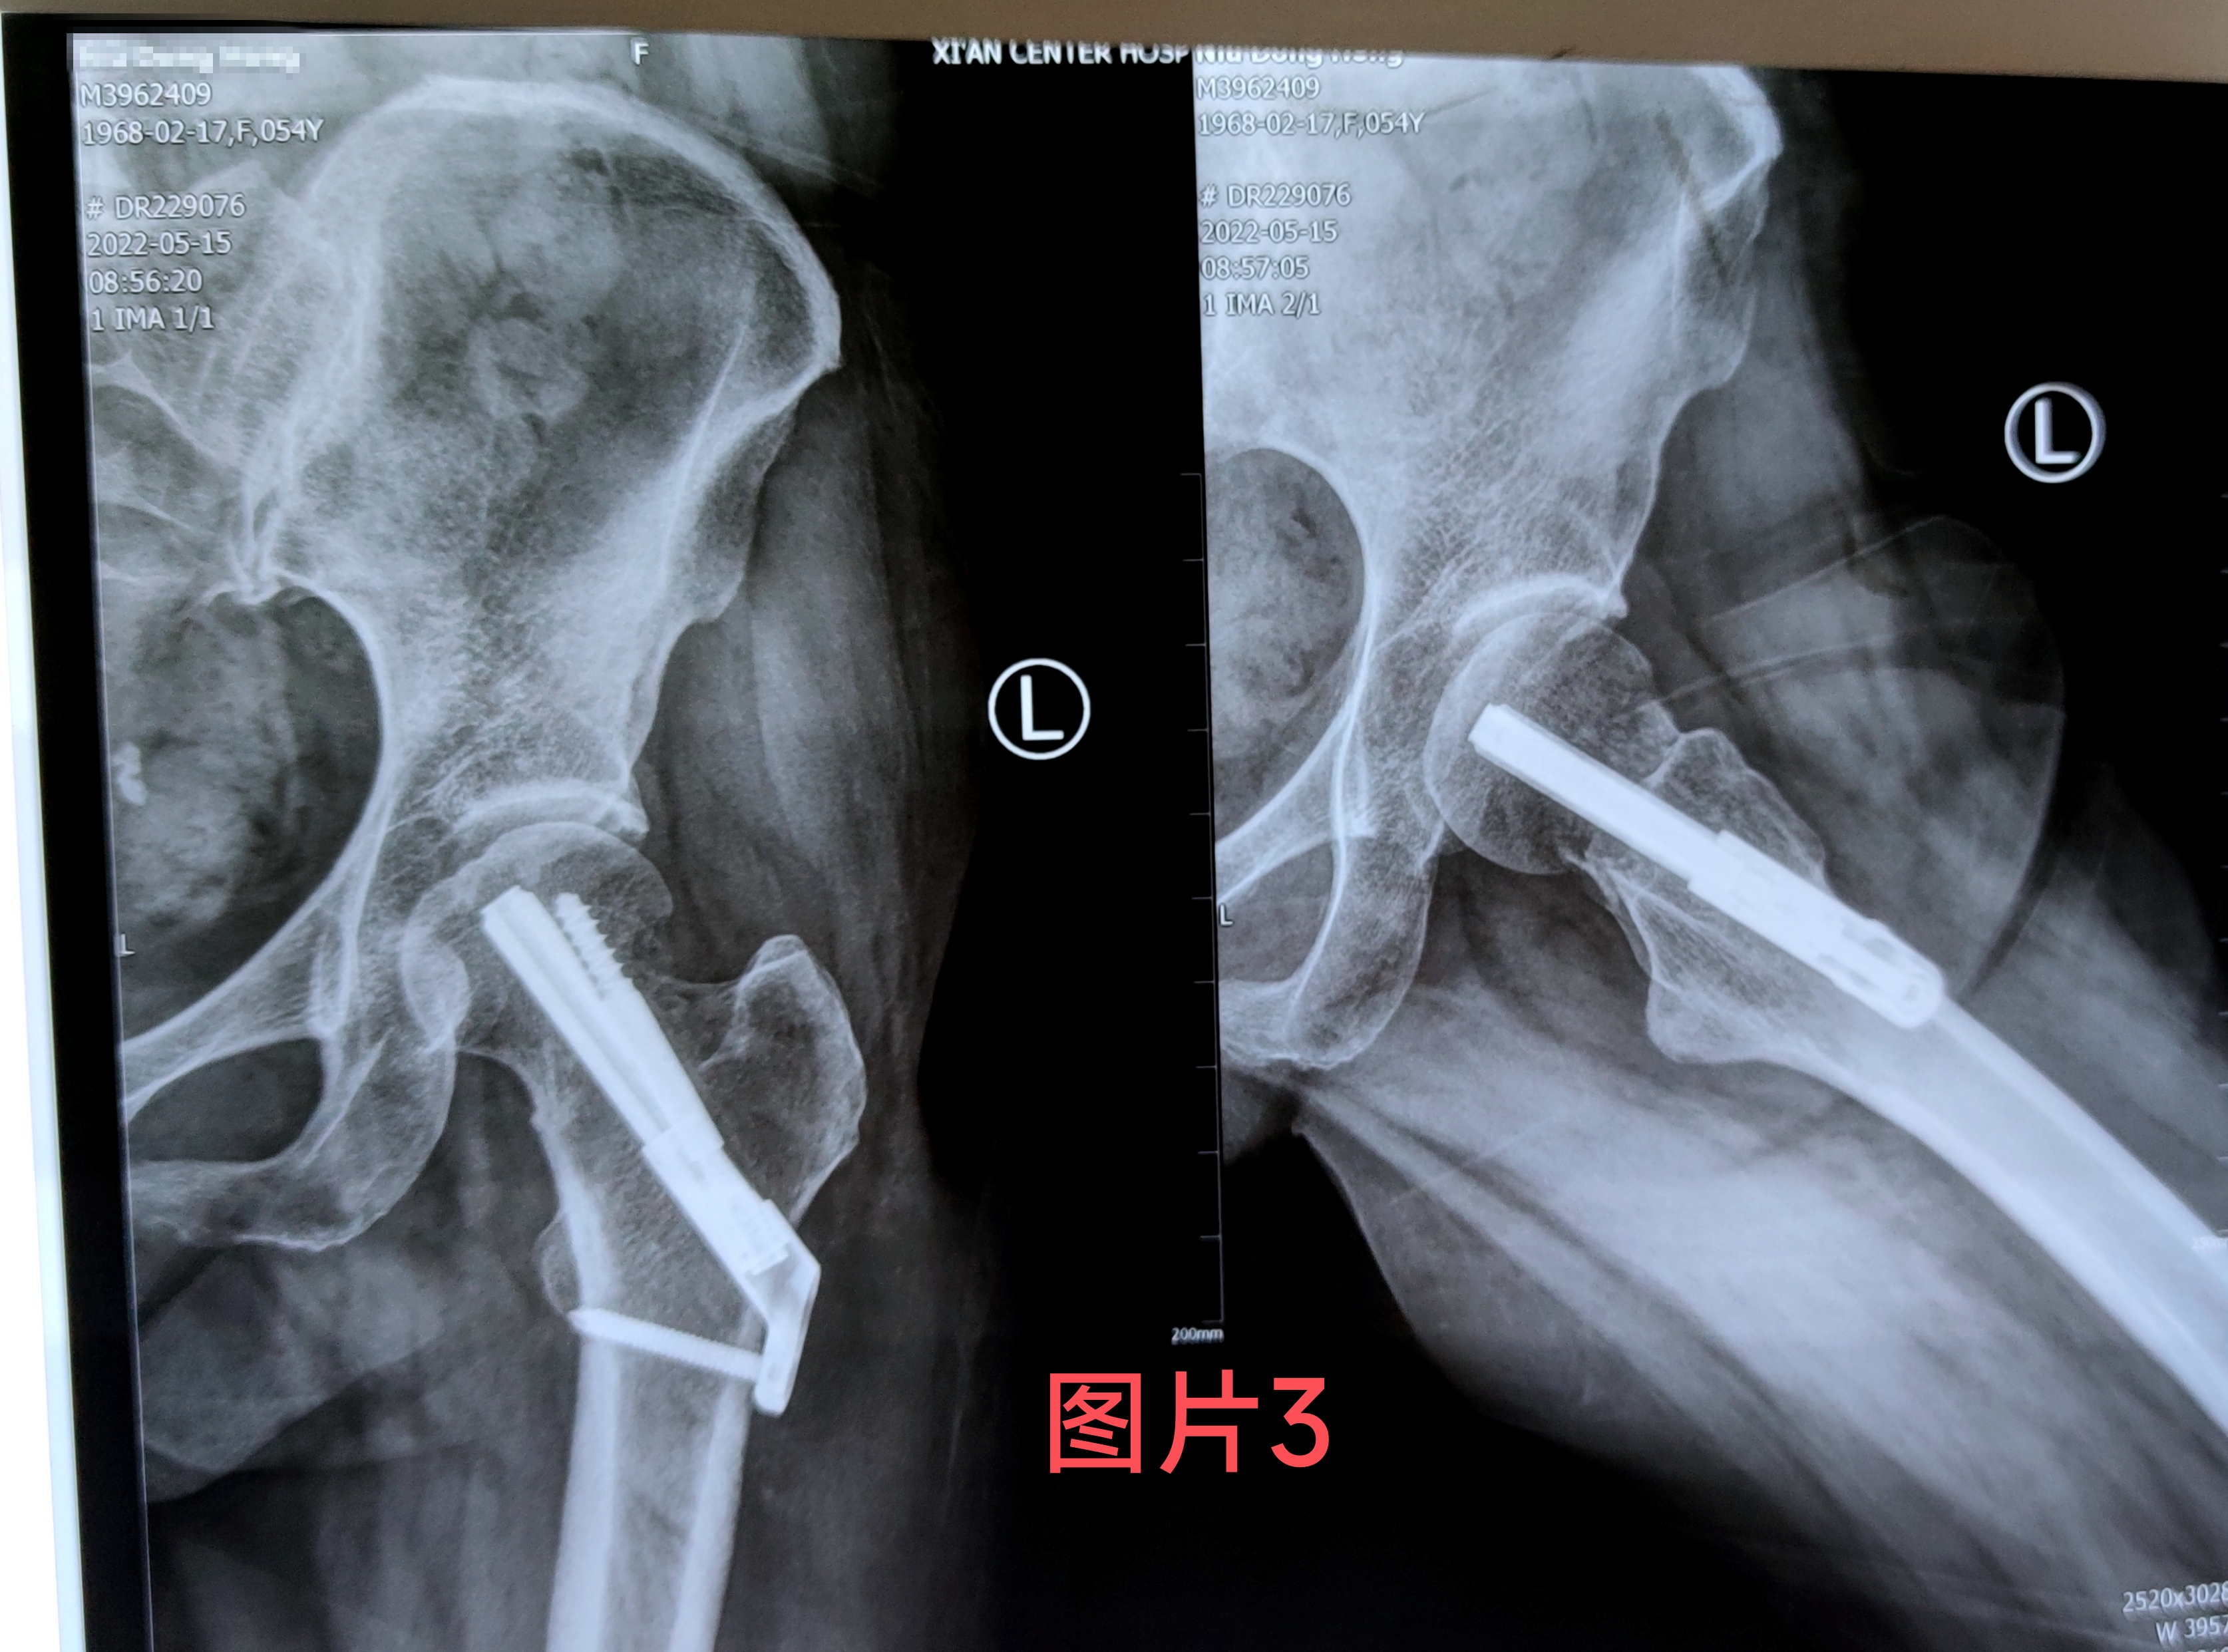

在做好相关术前准备后王涛主任医生为患者行骨折闭合复位FNS内固定手术,手术仅用半小时,手术切口3公分,手术创伤及时间比传统内固定手术大大减少,手术过程不对骨折周围血供产生干扰,最大可能地降低股骨头坏死的几率,术后当天患者无诉疼痛不适,随即开始功能锻炼。(图2)经一月复查固定牢靠,骨折无移位,无不适感(图3)。据王涛主任医生介绍股骨颈内固定系统(FNS)具有微创手术。时间短,创伤小,内固定支撑能力,防旋能力更为突出。具有力学稳定,滑动加压等优点,有利于患者早期恢复,降低股骨颈骨折不愈合发生率。王涛主任医生带领张磊卢洋主治医生治疗团队目前已为3例进行了此类手术均取得良好的手术疗效及治疗经验。填补了我院空白。